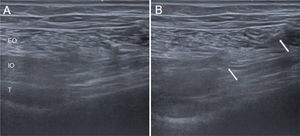

- 3

Infiltration. A fan-shaped injection is performed at three points within the muscle belly to ensure adequate distribution of the drug, using a 22 G needle. To facilitate the procedure, the needle should be directed obliquely from caudal to cranial rather than cranial to caudal, as the shoulder may hinder proper needle alignment in a horizontal plane. This is particularly the case in patients with PM syndrome, who often present with increased shoulder protraction, which limits access (Fig. 4).

- 4

Dosage. In the literature, the dose typically ranges between 20 and 50 U, although higher doses have been reported. We typically use 100 U, as we perform a single session with both therapeutic and diagnostic aims.